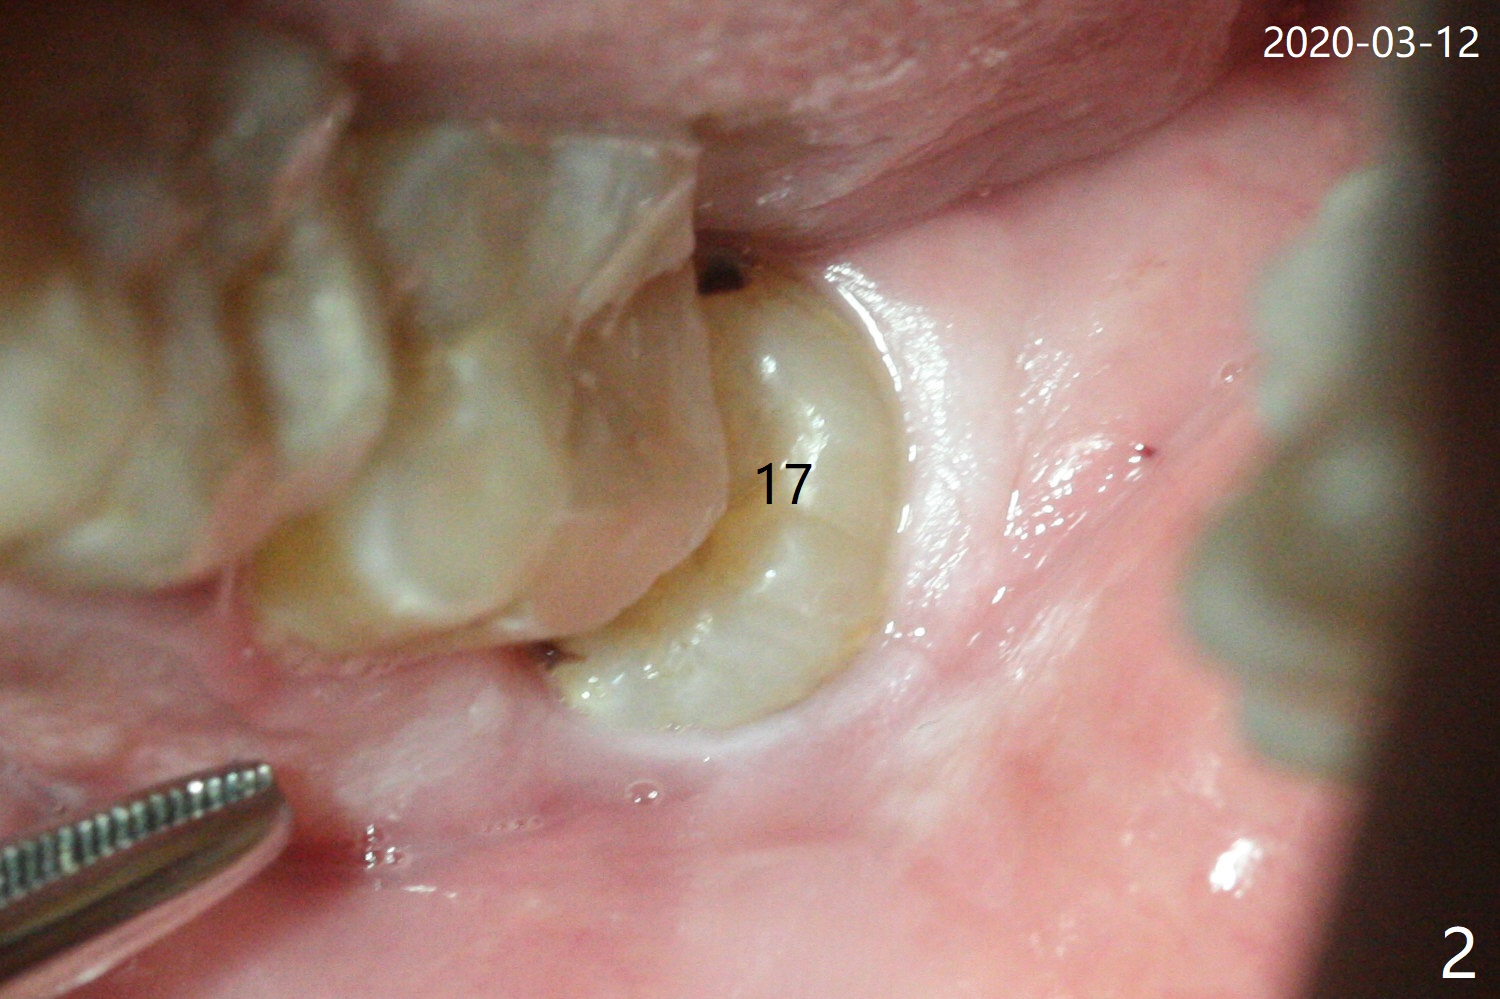

A 51-year-old man returns for #17 extraction 3.5 years post #32 one (Fig.1,2). The bone distal to #18 is lost severely (Fig.1). After #17 extraction and granu-lation tissue removal, Collagen Plug (Fig.3 C), Osteogen Plug (O) and cortical: cancellous (50: 50) mine-ralized allograft (.5-1 mm) saturated with ~ .2 ml of .3 mg/ml of rhPDGF-BB (B, one component of GEM21S) is placed in the socket. The patient returns with chief complaint of referring pain to the left ear 6 days postop, although the extraction wound looks fine. The mild pain (controlled by pain medication) persists 10 days and 1 month postop. The pain 1 month postop is associated with mastication. It appears that the tooth #18 is periodontally compromised. Occlusal equilibrium is required.